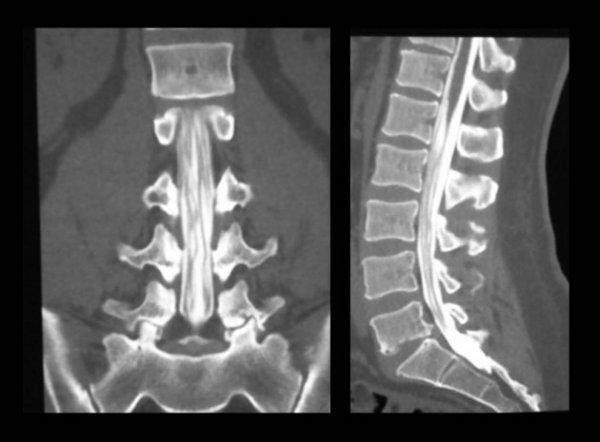

第五个,尾骨

这个东西的存在只是用来证明我们的祖先是有尾巴的……